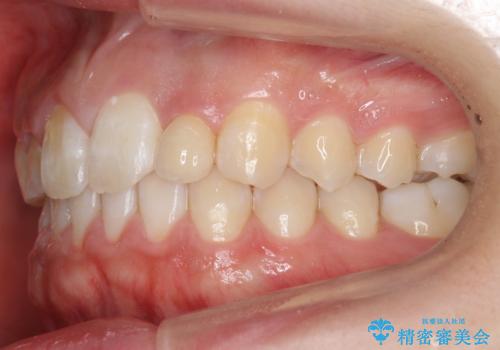

前歯のすきま 矯正治療とセラミックで小さな歯を形良く

- 前歯のすきまを気にして来院。

左上の2番が生まれつき小さく、スペースが余っていました。

右上の2番もやや小さめでしたが、相談の上、左上2番のみセラミックで形を整えることとしました。

そのほかの隙間はマウスピース矯正で閉じることにしました。